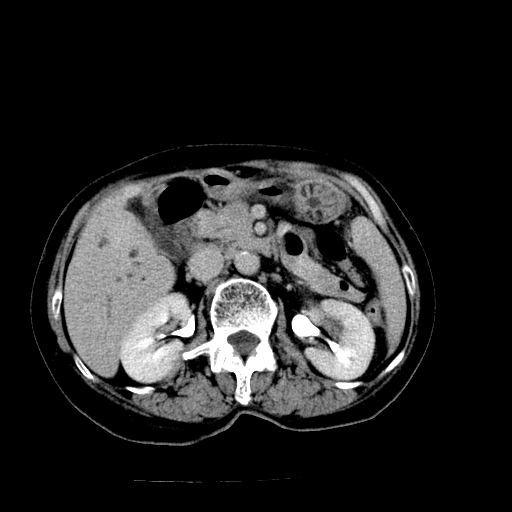

以下是引用卜一在2009-4-7 5:06:00的发言:[br]左右肝内胆管结石伴扩张合并胆系感染;不除外胆管细胞癌可能。支持! [br] [br]

以下是引用随光逐影在2009-4-7 8:21:00的发言:[br]肝内外胆管多发性结石并肝内外胆管扩张;胆系感染。